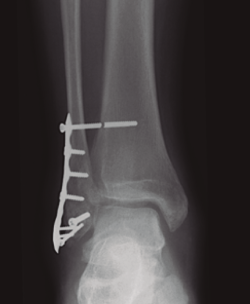

Una vez conseguida la reducción de la sindesmosis, debemos proceder a su estabilización y, en este sentido, pocos temas han despertado tanta controversia en la literatura reciente como el sistema ideal que mantenga en el tiempo de forma satisfactoria la reducción conseguida en el tratamiento inicial(6,7,8). El tornillo de fijación transindesmal o fijación rígida ha sido el método más utilizado y todavía hoy es considerado el patrón oro; sin embargo, en un intento de producir una reducción y fijación más anatómica, se han desarrollado en las últimas 2 décadas las denominadas técnicas de fijación dinámicas(7)(Figura 1).

Figura 1. Fractura del maléolo peroneo sintetizada con placa anatómica y sistema TightRope® a los 2 años de seguimiento con correcta reducción de la mortaja y la sindesmosis.